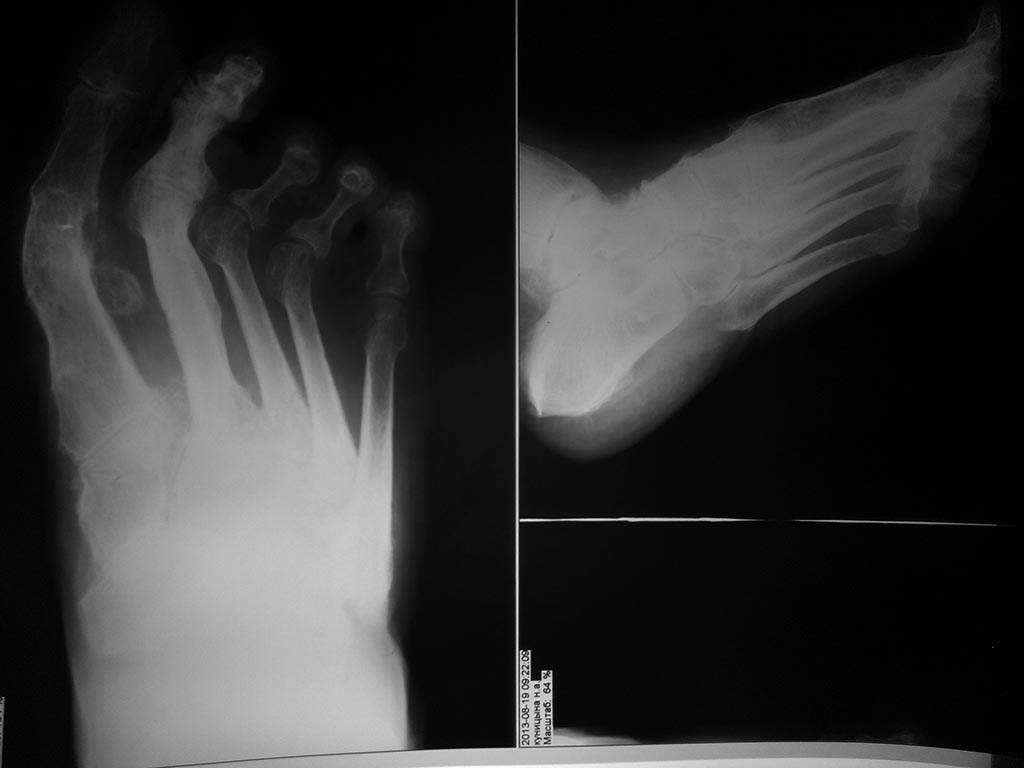

становится все актуальнее. Женщина после артродезирования 1 ПФС и неизвестного объема вмешательства на втором луче (но в обоих были спицы трансартикулярно) испытывает сильные метатарзалгии, второй палец ригидный и намного длиннее первого (прошу прощения за отсутствия фото in vivo!!!)... Какой объем операции на втором луче и других посоветовали бы подологи с учетом артрозов второго пальца, подвывихов 3-4 ПФС?